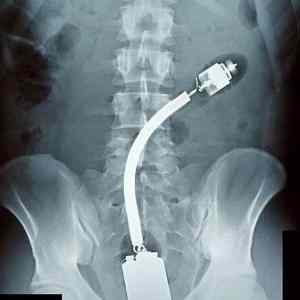

ale je to vibrátor, na konci motorek s excentrickým závažím

Vypada to jako HDMI->VGA redukce

Jednoduché - položíš si na břicho takéto dačo a jebneš se před RTG. A kamoš, co má zrovna službu, ti to udělá a tak vymýšlíte různé píčoviny.